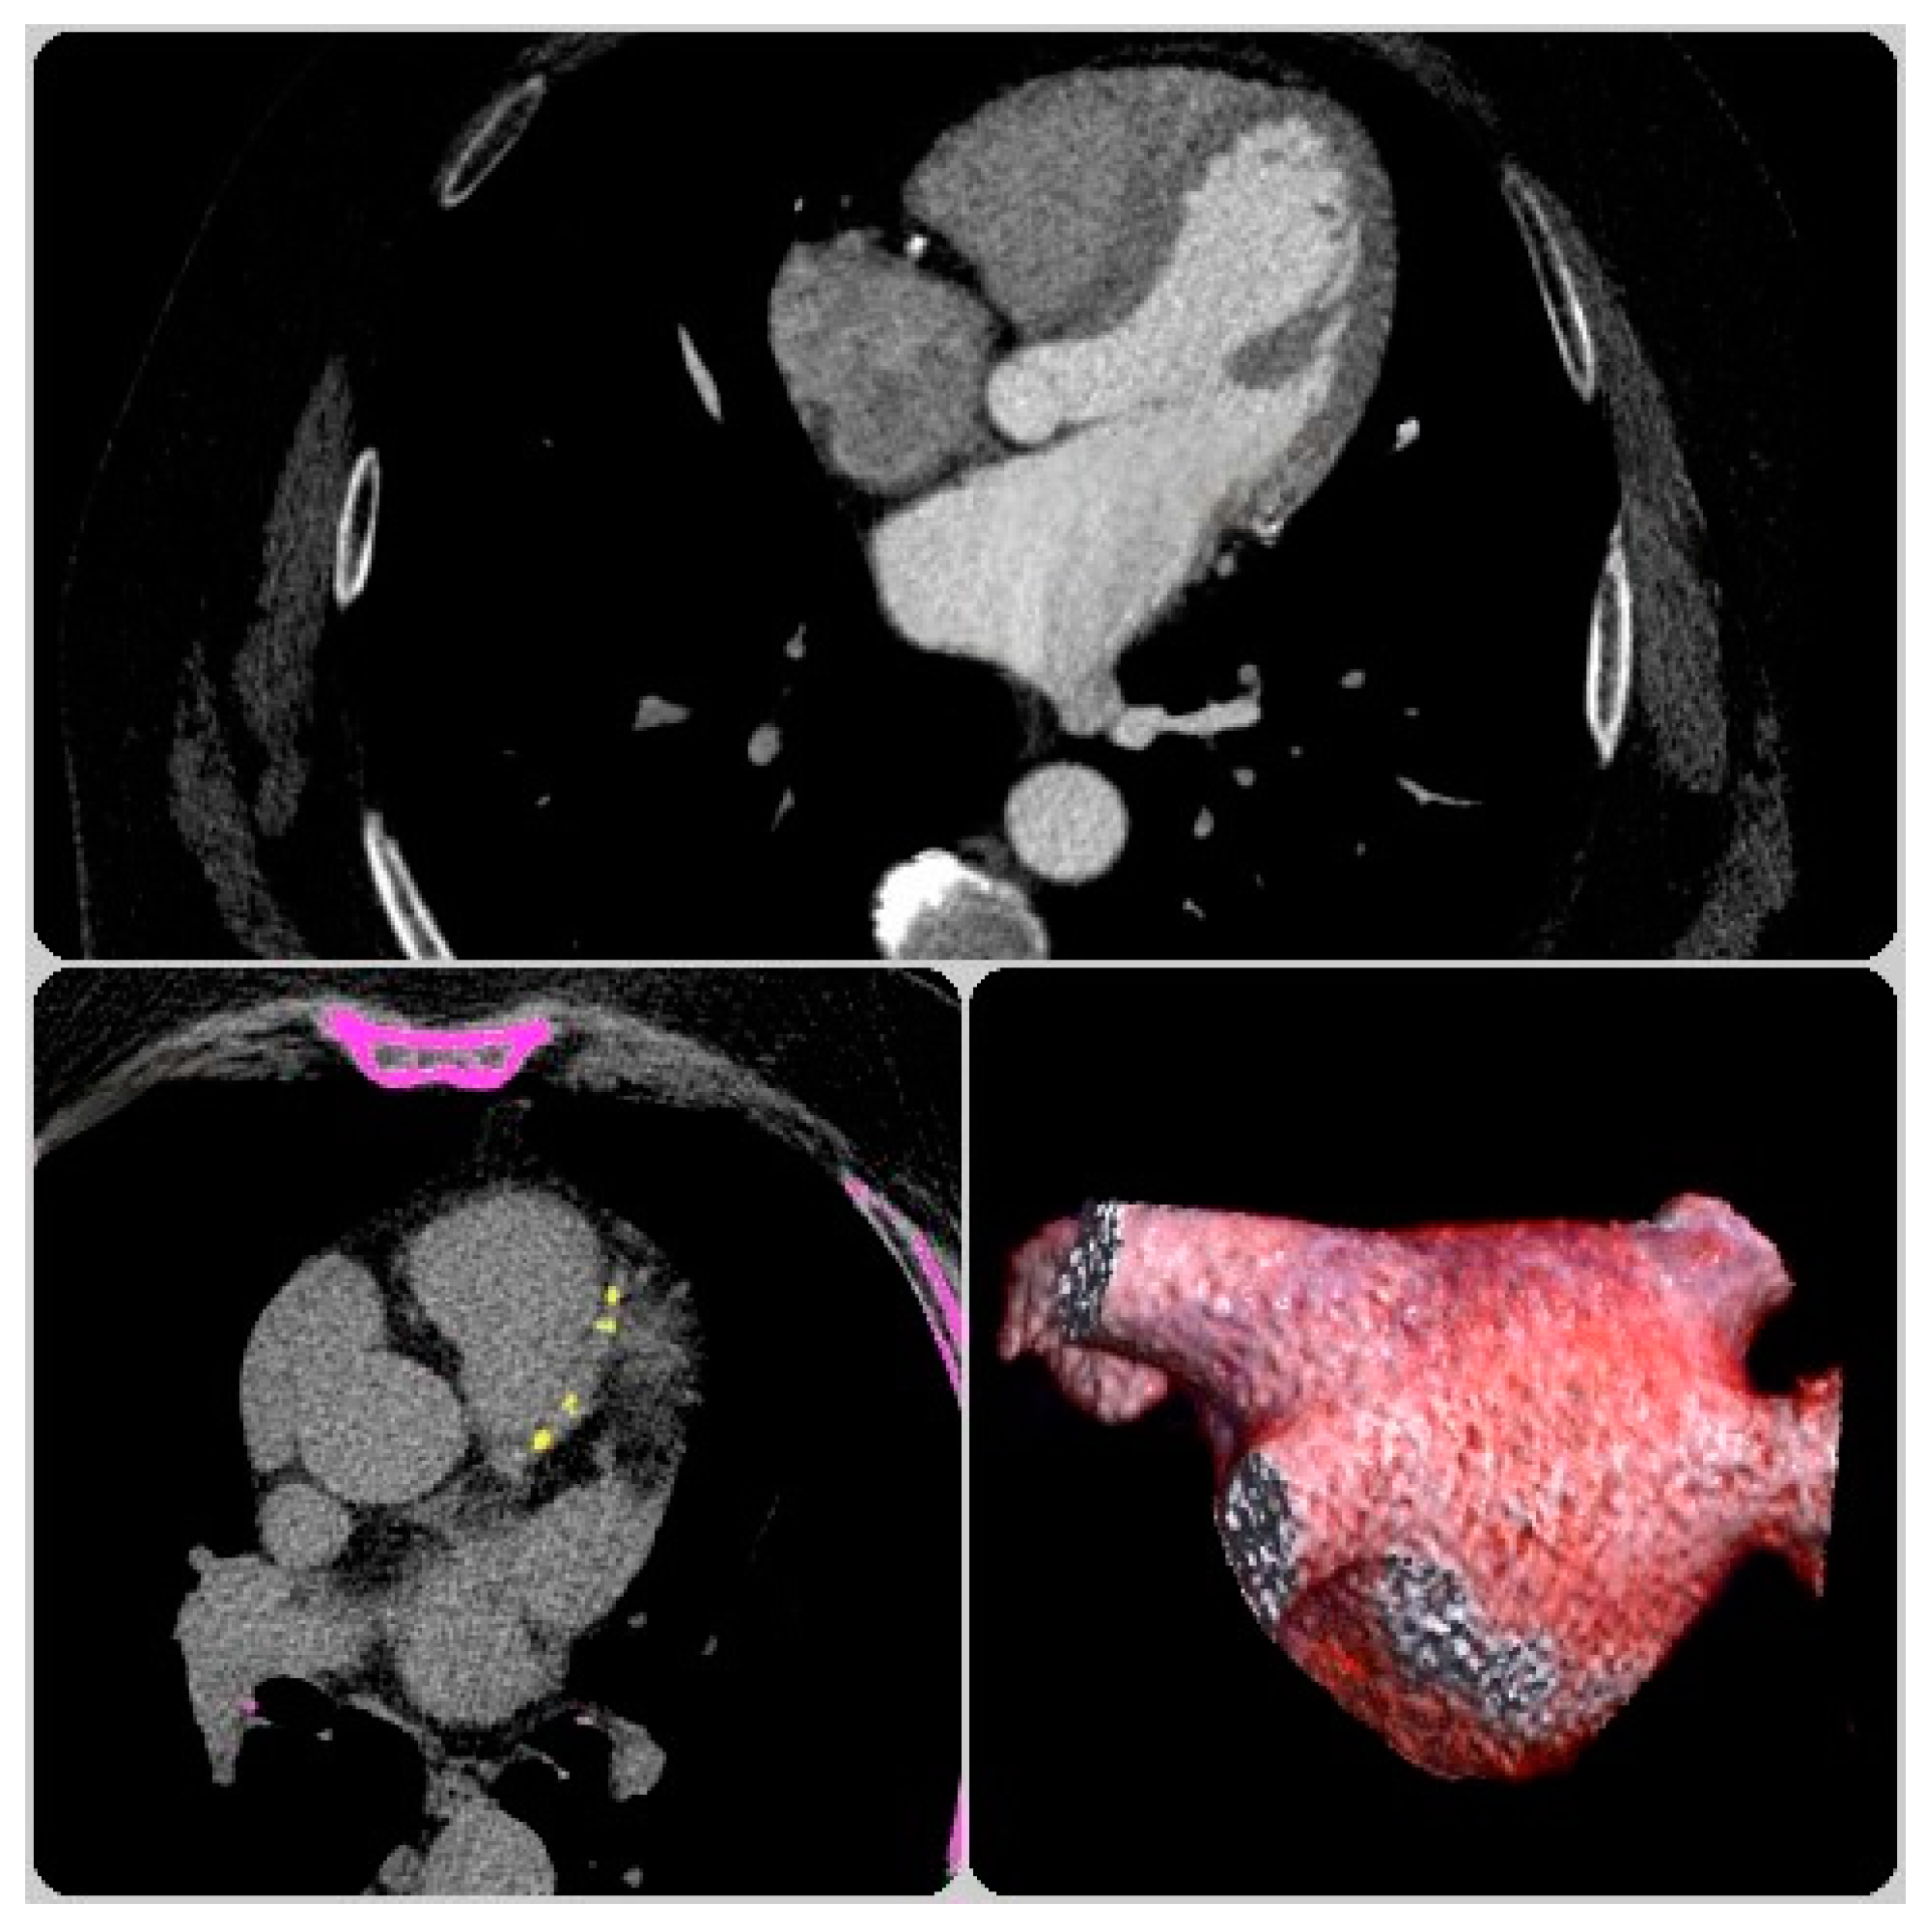

2.2.2. CCTA Analysis